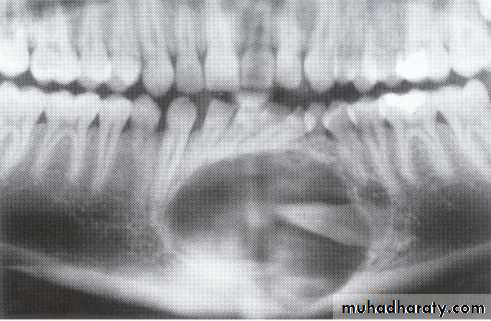

Ameloblasoma*Non-metastasizing tumor originating from remnants of the odontogenic epithelium of the enamel organ or dental lamina. *Associated with the crown of impacted teeth.

*80% located in the bicuspid & molar regions.

*Shape: is either unicystic or soap bubble-like lesion, Expansile, *Tooth migration is common,teeth in the area are vital.

*Adjacent teeth displaced, loosened , often resorbed

Extensive expansion in all dimensions

Maxillary lesions can extend into the paranasal sinuses, orbit or base of the skull.

Male > female.

Age; > 30 years